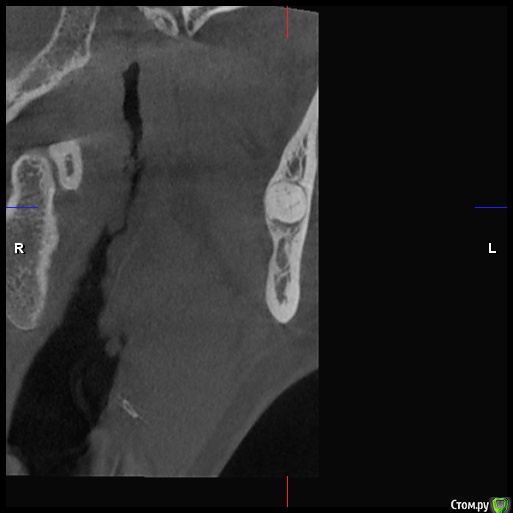

DenisV Опубликовано 18 декабря, 2019 Поделиться Опубликовано 18 декабря, 2019 Уважаемые коллеги, реферативный пациент, после химиотерапии окончил прохождение 2 месяца назад, хочет санировать полость рта (онколог разрешил), обнаружили образование на КТ в ретромолярной области слева. Какое Ваше мнение ? Направить к онкологу? Ссылка на комментарий

Lodkin666 Опубликовано 19 декабря, 2019 Поделиться Опубликовано 19 декабря, 2019 Мне кажется это похоже на сверхкомплектный зуб. Ссылка на комментарий

DenisV Опубликовано 19 декабря, 2019 Автор Поделиться Опубликовано 19 декабря, 2019 Мне кажется это похоже на сверхкомплектный зуб.неоднородной плотности, напрятали это зуб Ссылка на комментарий

Jurai Опубликовано 22 декабря, 2019 Поделиться Опубликовано 22 декабря, 2019 кажется, что зачаток сверхкомплектного или одонтома. Узнайте у пациента нет ли у него снимков прошлых лет - сравнить со свежим. Ссылка на комментарий

Irouil Опубликовано 22 декабря, 2019 Поделиться Опубликовано 22 декабря, 2019 Согласен, похоже на одонтому, чёткая капсула, плотность дентина 2 Ссылка на комментарий